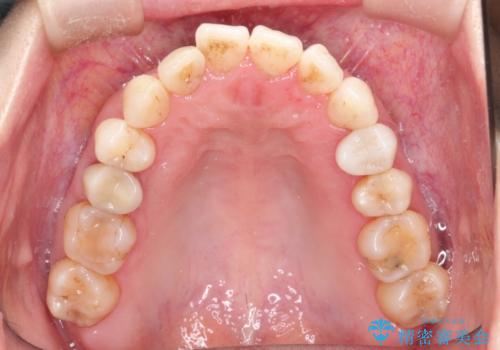

【インビザライン 】前歯を下げたい

- 前歯の凸凹と、前突を主訴に来院されました。

インビザライン にて治療を行なっております。

治療期間中はゴムかけを行なってもらうことで、前歯を下げることができました。